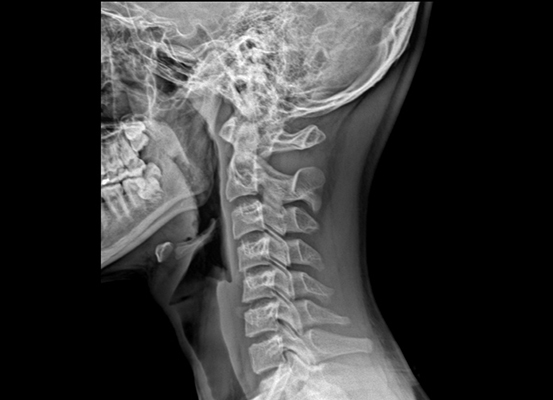

우선 목디스크란 목뼈 사이의 디스크가 깨지거나 상해 일어나는 질환을 의미합니다. 디스크는 척추뼈 사이에서 충격을 흡수하고 신경을 보호해주는 역할을 하는데, 디스크가 손상되면 신경이 압박되어 통증, 저림, 마비 등의 증상이 보여집니다.

목디스크의 증상은 여러종류가 있으며 환자마다 그 증상이 같지않게 생겨날수 있습니다. 최고 흔한 증상으로는 목의 통증입니다. 목의 통증은 목 뒤쪽, 어깨, 팔, 손까지 뻗쳐서 일어날 수 있습니다. 거기에다가, 저림, 마비, 감각 이상, 손발의 힘 저하 등의 증상이 발생할 수 있습니다.

우리의 목은 인체에서 무척 요긴한 역할을 합니다. 머리를 지지하여 돕고, 머리를 움직여 시야를 확보하는 역할을 히며, 척추의 시작 부분으로서 척추를 지켜주고, 척추를 통해 뇌와 인체의 다른 부분으로 신경을 보급하는 역할을 합니다.